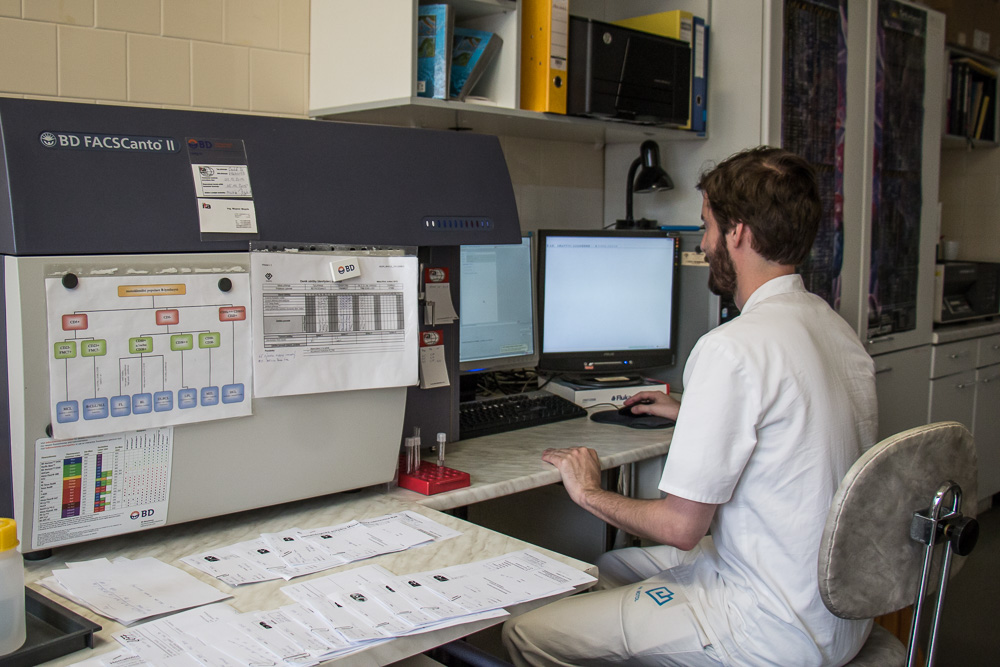

Ústav patologie a molekulární medicíny se zabývá komplexní laboratorní diagnostikou nádorových a nenádorových onemocnění. Využívá metod klasické histologie a cytologie s navazujícími dalšími speciálními laboratorními vyšetřovacími metodami. Ty zahrnují: pohled do buněk a tkání na úrovni ultrastrukturální analýzy (elektronová mikroskopie), průkaz exprese proteinů (metody imunohistochemické, Western blot, průtoková cytometrie), průkaz enzymové aktivity ve tkáňových řezech (enzymová histochemie), analýzu změn na úrovni chromozómů a genů a průkaz některých virů v histologickém řezu (metody in situ hybridizace) a rozbor DNA a RNA extrahovaných ze tkání (metody kvalitativní a kvantitativní polymerázové řetězové reakce, sekvenování). Vyšetřovaným biologickým materiálem jsou tkáně (nativní, zmrazené, fixované), punktáty kostní dřeně, periferní krev, případně jiné buněčné tekutiny (výpotky) a autologní štěpy pro transplantaci kostní dřeně.

Diagnostikou onemocnění různých systémů se zabývají týmy školených pracovníků – lékařů a biologů s pomocí laborantek ve specializovaných laboratořích.